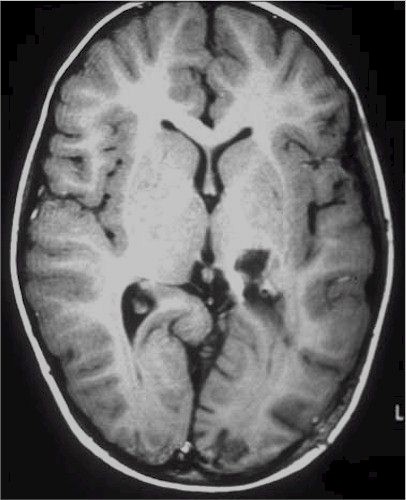

Chirurgia

dei tumori a basso grado |

| Il termine basso grado significa una crescita estremamente lenta. Per quanto nel tempo l'ingrandimento è molto lento il rischio maggiore è che la lesione si trasformi in una lesione di alta malignità per cui l'evoluzione diventa poi estremamente rapida.

Queste lesioni si presentano con una conformazione anatomica che varia da forme molto circoscritte dove è possibile un'asportazione radicale a quelle estesamente infiltranti dove può essere indicata solamente una biopsia per l'accertamento diagnostico.

Noi sappiamo che allo stato attuale delle nostre possibilità terapeutiche, il migliore risultato per il paziente è l'asportazione quanto più radicale della lesione.

Trattando una lesione relativamente circoscritta, a volte difficile da distinguere dalla struttura circostante, diventa di estremo aiuto l'uso di sistemi stereotassici o di neuronavigazione che ci permettono una chirurgia guidata da un sistema computerizzato. Tale metodica ci permette di pianificare prima e di conoscere durante l'intervento la posizione del chirurgo rispetto a quelli che sono i margini del tumore e del parenchima sano. In questo modo è possibile raggiungere qualsiasi sede consentendo un'asportazione controllata della lesione senza esporre ad eccessivo rischio le strutture circostanti.

RM preoperatoria

|

RM

postoperatoria